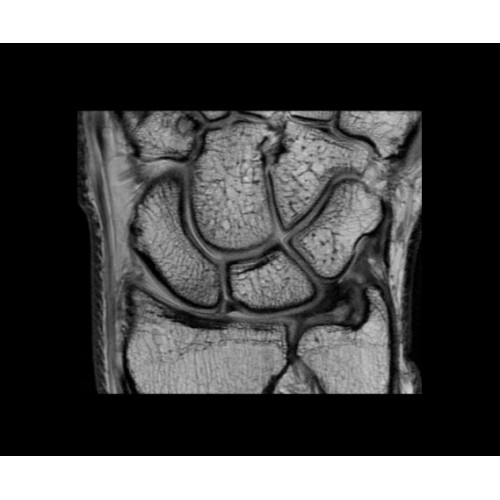

В систему SIGNA PET/MR встроены запатентованные детекторы кремниевого фотоумножителя (SiPM) и сверхчувствительные кристаллические сцинтилляторы на основе лютеция толщиной 25 мм. Благодаря этому обеспечивается исключительная чувствительность и возможность использования времяпролетной диагностики (TOF).

Кроме того, в результате использования технологии TOF и инновационной технологии реконструкции Q.Clear вы сможете добиться прекрасного соотношения сигнал/шум. А благодаря технологии нулевого времени эхо (ZTE) визуализировать костную структуру без ионизирующего излучения. Все эти разработки для улучшения качества сканирования и точности анализа помогут вам использовать весь потенциал ПЭТ/МРТ.

• Легкий герметичный радиочастотный экран с медным покрытием.

• Современные кристаллический сцинтилляторы на основе лютеция (LBS) с усовершенствованными спектральными отражателями (ESR).

• Кремниевые фотоэлектронные умножители (SiФЭУ).

• Термопроводящая подкладка.

• Алюминевая монтажная пластина.